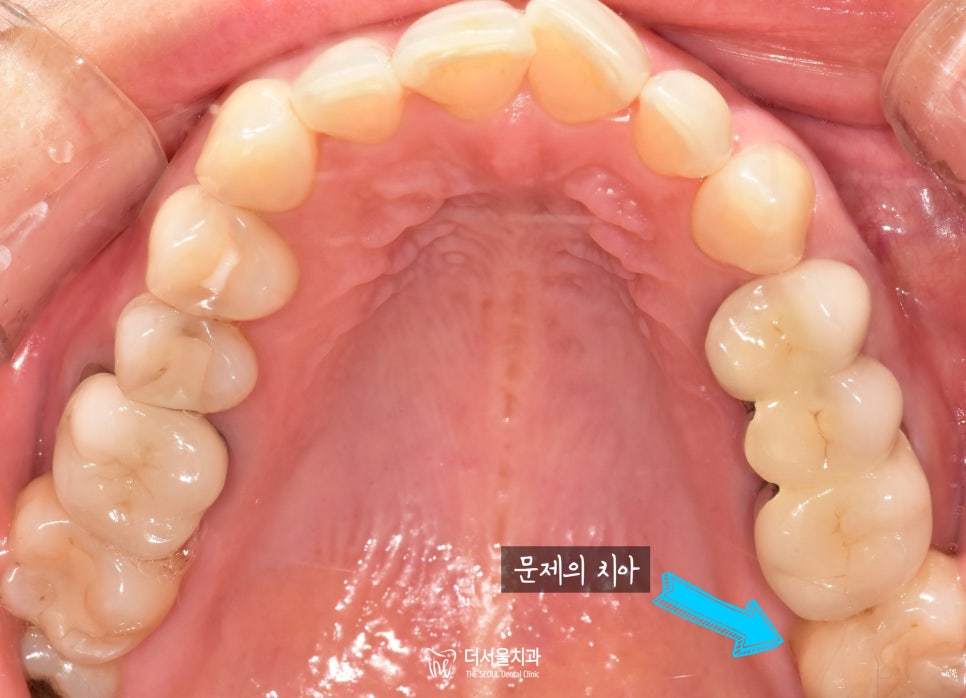

먼저 구강 내를 살펴보았을때,

큰 문제는 없는듯 했습니다.

시커멓게 썩었다라든지

눈에 띄는게 없었으니까요.

그래서 파노라마(X-Ray) 촬영에 들어갔습니다.